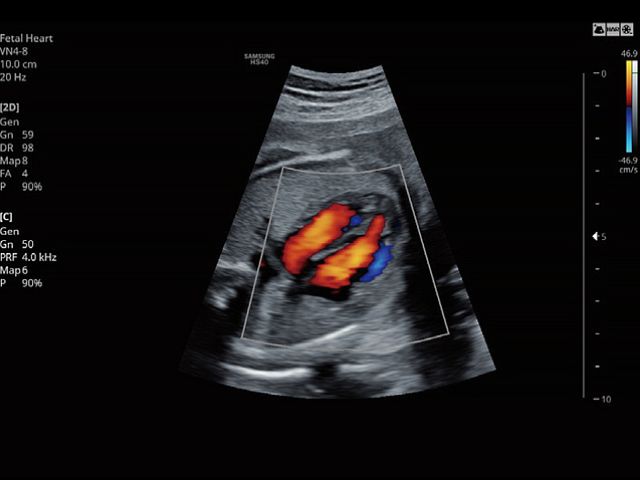

5D NT™ provides the midsagittal plane view automatically by rotating and magnifying the images when measuring the nuchal translucency (NT) of the fetus in early weeks.